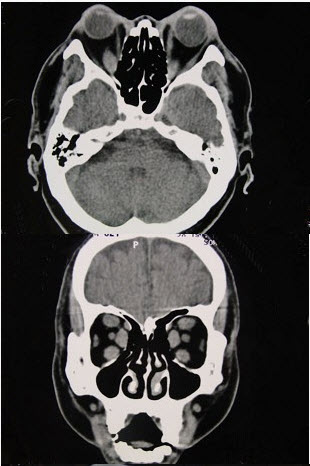

女性50岁,消瘦、多饮多食,脖子粗大,双侧眼球突出,一年余,CT检查如图所示,应考虑为()。

A、眼型格氏病

B、甲状腺眼病

C、炎性假瘤

D、横纹肌肉瘤

E、眶部结核

B